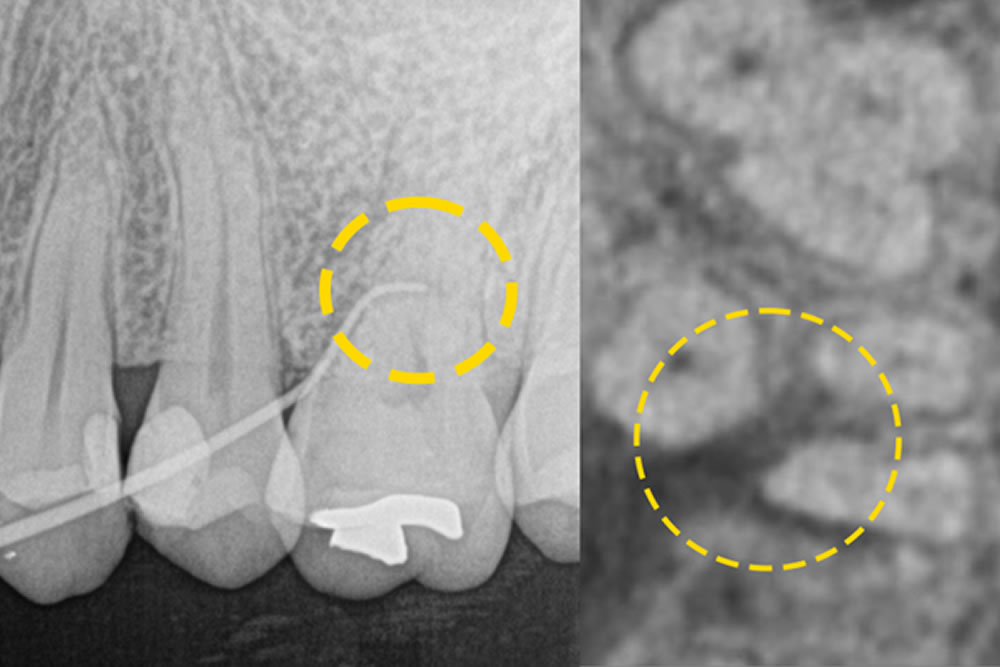

- 3.1 重症化した歯周病を手術なしで治療した症例

- 3.2 グラグラする歯を手術なしで治療した症例

- 3.3 他院で抜歯と診断された歯を手術なしで治療した症例

- 3.4 骨を部分的に欠損した歯を手術なしで改善した症例

まずは、論より証拠。日本歯周病学会専門医である当院の院長が実際に行った「重度歯周病で抜くことになる確率が高い歯を抜かなかった歯周病改善例」をご紹介します。

初診時(上写真)、右下6番目の歯は今にも抜け落ちそうな状態でしたが、重度歯周病治療【MINST】によって、症状を改善し、術後1年後(下写真)には歯周組織もしっかりと再生しました。

※外科処置なし・再生材料も使用しておりません。